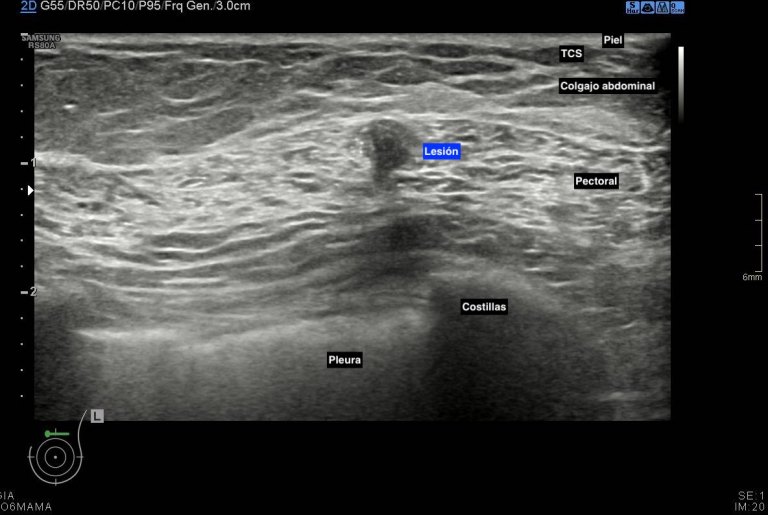

Durante la exploración se observan cambios secundarios a mastectomía bilateral, pero en línea intercuadrántica superior de mama izquierda, en el espesor del musculatura pectoral vi un nódulo hipoecogénico de 6 mm de bordes irregulares (imágenes 2 a 5) que me pareció muy feo, me asusté y aunque no era palpable inmediatamente se lo comenté a la doctora encargada de la exploración, lo calificó de Birads 4C y le pidió resonancia magnética.

Lo primero de todo la anatomía de la ecoestructura, es vital para comprender lo que se ve. Además ligada con la semiología, puedes ver como la grasa de la reconstrucción con colgajo abdominal es muy parecida a la grasa normal que puedes encontrar en la mama que no ha sido intervenida. Siempre tener una visión global de la ecoarquitectura, conocimiento de la normalidad de todos los tejidos englobados en la ecografía y eventual mamografía de la mama para poder localizar cambios anómalos.

Tras los estudios posteriores realizados como ampliación de estudio, arrojaron cambios postquirúrgicos en el pectoral que explicaban la imagen descrita anteriormente y que puedes ver en la imágenes que te he puesto.

Afortunadamente fueron buenas noticias, el resultado fue benigno a pesar de la alta sospecha, a consecuencia de los cambios posquirúrgicos que afectaban a la porción muscular de la exploración ecográfica. Siempre en mamas operadas los cambios postquirúrgicos pueden ofrecer zona llamativas, nosotros siempre atentos y ante cualquier duda lo dejamos reflejado en el pre-informe o se lo contamos directamente a la radióloga responsable, nunca nos quedamos con dudas, siempre documentar los hallazgos correctamente con máxima calidad de imagen, siempre es nuestra carta de presentación.